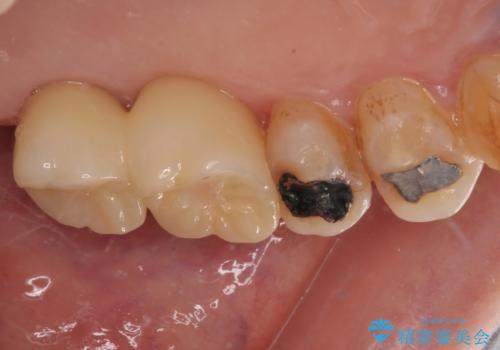

骨量の少ない上顎大臼歯 骨補填材を用いない短期間インプラント治療

しかしながら、ここ数年で流通してきたデンサーバーというドリルと、エキストラワイドショートインプラントの併用により、骨補填材による上顎洞底の挙上なしに埋入が行えるようになりました。

元々の骨量が少なく、通常よりは待機期間が長くなりますが、数ヶ月程度で補綴治療まで行うことができるため、こちらの手法でインプラント補綴治療を行うこととしました。

インプラントが待機期間に脱落することがありますが、一切のトラブルなく、最短期間で無事に治療を終えることができました。